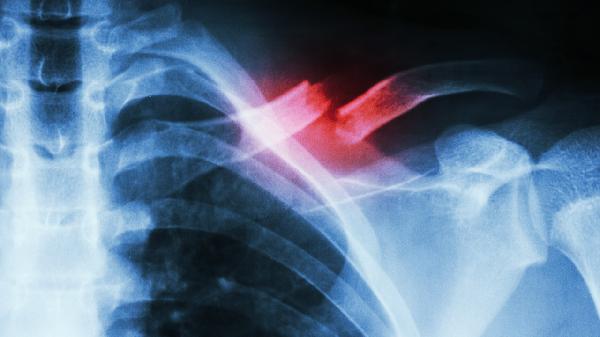

锁骨中段血供相对薄弱,粉碎性骨折或严重移位可能破坏滋养血管。骨折端缺血会导致成骨细胞活性降低,表现为持续疼痛和异常活动。需通过CT评估骨痂形成情况,必要时采用带血管蒂骨移植术促进愈合,如使用同种异体骨修复材料结合锁定钢板固定。

保守治疗时八字绷带固定不牢固,或内固定术后钢板螺钉松动,均会导致骨折端微动。持续机械刺激使纤维组织替代骨痂,临床可见患侧肩关节活动时骨擦感。需手术更换为解剖型锁骨锁定钢板,术后配合肩关节外展支具限制活动。